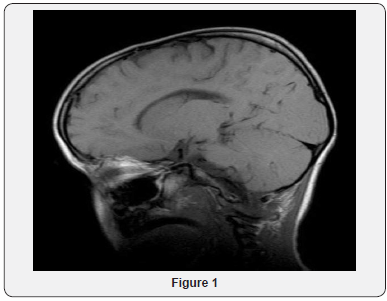

A boy who developed normally for the first 2 years. At the age of two years and 9 months, he developed an episode of unsteadiness in the morning and had some difficulty raising his head with eye crossing for a short period of time, which resolved spontaneously. Then, there was deterioration in his milestones and skills with episodes of dystonia. A massive deterioration occurred after he developed high grade fever, with decreased tone and hyper-extension of the neck, with episodes of lowered consciousness level and seizures. He was not able to turn his head with generalized hypotonia and bilateral brisk reflexes. The patient was admitted in our hospital and during the initial episodes’ electroencephalography disclosed the presence of diffuse slowing and the absence of consistent background activity. Results of extensive laboratory investigations (e.g., complete blood count, serum routine chemistry, glucose, amino acids, lactate, acylcarnitines, urine gas chromatography-mass spectrometry, thyroid functions, creatinine kinase ammonia, very long chain fatty acids and pyruvate) were all within normal limits. Lumbar puncture and cultures of cerebrospinal fluid were negative. Also results of peripheral blood for neuronal ceroid lipofuscinoses (NCL) and mitochondrial DNA mutation analysis did not show any abnormality. Initial magnetic resonance imaging (MRI) and magnetic resonance spectroscopic (MRS) revealed no definite abnormality (Figures 1-3).